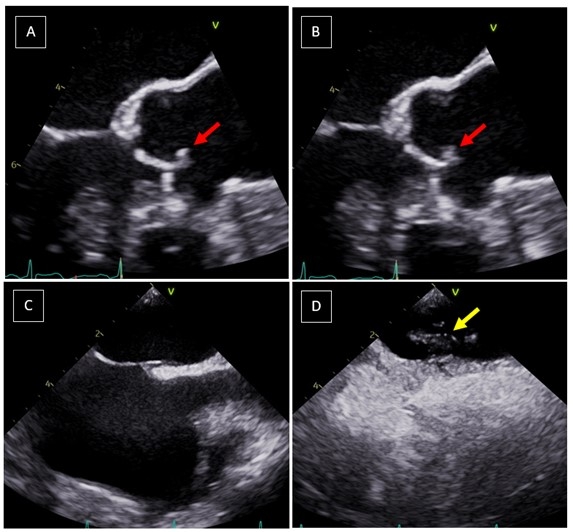

Case Description: A 69-year-old female presented with left sided facial droop, slurred speech and left arm weakness. A computed tomography angiography revealed focal occlusion of the distal right middle cerebral artery. She was initiated on thrombolytic therapy and experienced resolution of symptoms. Transthoracic echocardiogram revealed right to left shunting consistent with a patent foramen ovale (PFO). Further workup with TEE confirmed the presence of a PFO but also detected a mobile echogenic mass on the aortic valve leaflet, indicative of papillary fibroelastoma (PFE). Cerebral infarction was attributed to an embolic event, with the PFO and PFE being likely culprits.

Discussion: Current guidelines give a conditional recommendation, low certainty of evidence, for PFO closure in adults older than 60 years, although some observational studies have shown some risk reduction in older patients. The key trials showing clinical benefit of PFO closure were in adults younger than the age of 60. For left sided cardiac tumors, such as PFE, guidelines give a 2A recommendation for resection. Addressing the risk for recurrent stroke in this 69-year-old patient was an essential part of stroke care, as such, a multi-disciplinary team of experts including cardiology, neurology, and cardiothoracic surgery was conveyed. The decision was to proceed with surgical intervention in addition to antiplatelet therapy to achieve optimal risk reduction. The patient subsequently underwent successful surgical removal of the PFE with native valve preservation and PFO closure.

Conclusion: Cardiac PFEs and PFOs can be associated with increased stroke risk. Employing appropriate imaging techniques and timely interventions are of utmost importance in stroke management.